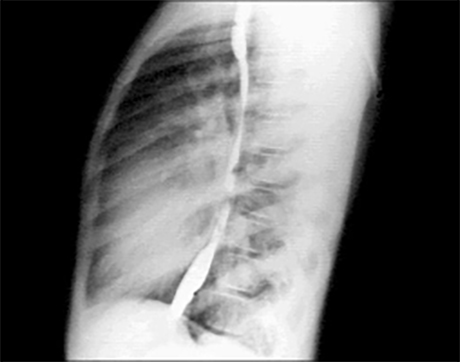

PA and Lateral

Click on the Xrays to enlarge them.